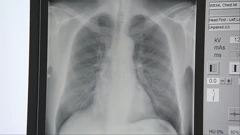

Pušenje je jedan od najvećih javnozdravstvenih izazova današnjice - odgovorno za milijune smrti svake godine. Svjetska zdravstvena organizacija uskoro će obznaniti preporuke koje bi mogle iz temelja promijeniti svakodnevne navike milijuna pušača diljem svijeta.

Više od 7 milijuna smrti godišnje veže se uz uporabu duhana

- Ta uporaba uzrokuje goleme štete, tu govorim i o bolestima i invaliditetu i smrtima. Možemo reći da se više od 7 milijuna smrti godišnje veže uz uporabu duhana, govori Pejnović Franelić.